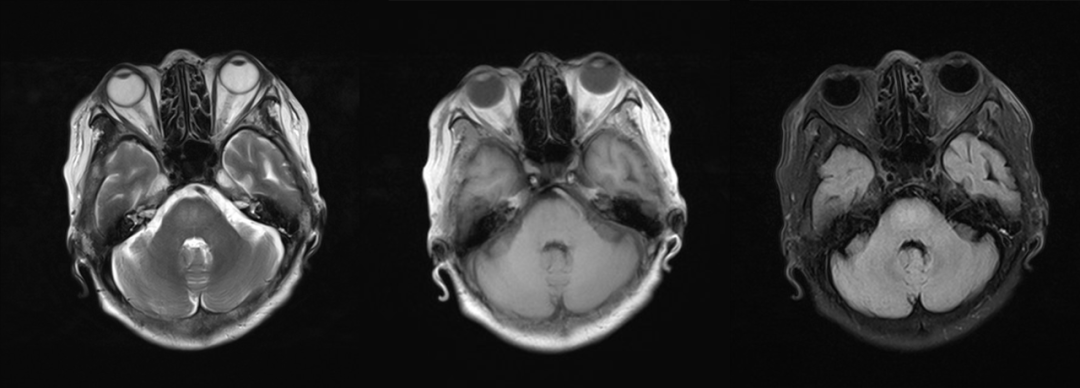

(2)CPM,病灶多位于桥脑基底部而桥脑腹侧不受累,病灶形状多种多样,可为条片状(位于中脑基底部中线,如本例)、斑片状、圆形或卵圆状、「三叉戟」或「猪鼻」样,T1WI 呈低信号,T2WI 及 FLAIR 呈高信号,病灶边界清晰,部分患者出现 DWI 高信号,有利于疾病的早期发现,出现强化提示血脑屏障破坏。

“三叉戟”样病灶,桥脑腹侧及被盖未受累

“猪鼻”样病灶,桥脑腹侧及被盖未受累,中脑被盖束未受累(蓝箭头)

圆形病灶,位于桥脑基底部,桥脑腹侧及被盖未受累